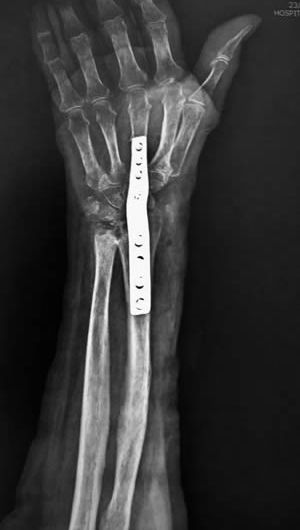

Lesiones del Carpo

El carpo es una zona anatómica extremadamente compleja, no solo se refiere al túnel del carpo (lesión de nervio mediano) sino se refiere a la parte que es en realidad la muñeca, la unión entre el antebrazo y la mano, y es la responsable de que podamos abrir una lata, una botella, atornillar algo, prácticamente todos los movimientos de la muñeca están a expensas del buen funcionamiento de estos ocho huesos y sus ligamentos.

Principalmente tenemos dos tipos de lesiones; las fracturas y las lesiones ligamentarias. Todas deben ser tratadas de forma oportuna y de ser posible con la mejor tecnología, como en muchas otras patologías de la muñeca y mano, vamos de lo simple a lo complejo, sin embargo los resultados de una reparación abierta pueden ser muy buenos, la recuperación de esa misma lesión al ser operada con una técnica cerrada, como es la artroscopia nos permitirá un retorno mas pronto a las actividades cotidianas.